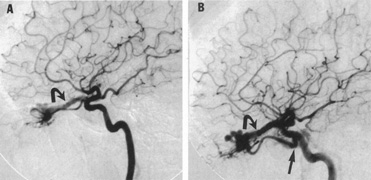

The therapy for AVMs has been reviewed elsewhere.91–93 The preferred treatment remains complete surgical excision of the malformation. However, significant advances in endovascular and radiosurgical techniques have resulted in a marked increase in the use of multimodal, staged approaches to AVM treatment. A variety of intravascular techniques use embolization91 with materials such as particles of polyvinyl alcohol (PVA), platinum coils, and injection of liquid N-butyl-cyanoacrylate (NBCA) adhesive (Fig. 11). Complications of intravascular embolotherapy include vessel perforation by the catheter, migration of embolic materials, and infarction and hemorrhage of normal brain.

Fig. 11. Embolization of middle cerebral vessels that supply occipital lobe arteriovenous malformation (AVM). The patient had a subarachnoid and intraparenchymal hemorrhage that produced a left homonymous field defect. A: Right carotid arteriogram demonstrates contribution via posterior communicating artery to a right occipital lobe AVM. B: Vertebral injection. The arrow points to the enlarged right posterior cerebral artery that is a major feeder of the AVM. C: Right carotid arteriogram during glue embolization procedure. The arrow points to a catheter as it traverses the segment seen in (B). The catheter was advanced via the internal carotid artery but is positioned far posteriorly. D: Upper branches to the AVM now are occluded, with residual low-flow vascularization via the middle cerebral artery. E: Skull film showing radiopaque glue within the AVM and blood vessels previously supplying it. The patient had a persistent visual field defect but greatly reduced headache and no persistence of subjective bruit. (Courtesy of Dr. Joseph Horton.)